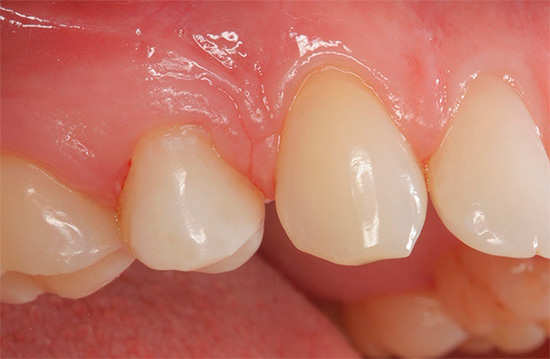

La carie dentale è accompagnata da una violazione dell'integrità del dente con la formazione di una cavità. Tuttavia, non pensare che un foro sarà necessariamente visibile nel tuo dente: spesso una cavità cariata non viene visualizzata e può essere trovata solo all'appuntamento del dentista quando si sonda un dente con uno strumento speciale per diagnosticare la carie.

Tuttavia, ci sono casi abbastanza comuni in cui il paziente stesso vede una formazione di cavità nel dente, poiché con la carie della dentina il quadro clinico è piuttosto ricco di sintomi associati. Questi includono:

- Imperfezione estetica, soprattutto quando il dente anteriore inizia a decadere.